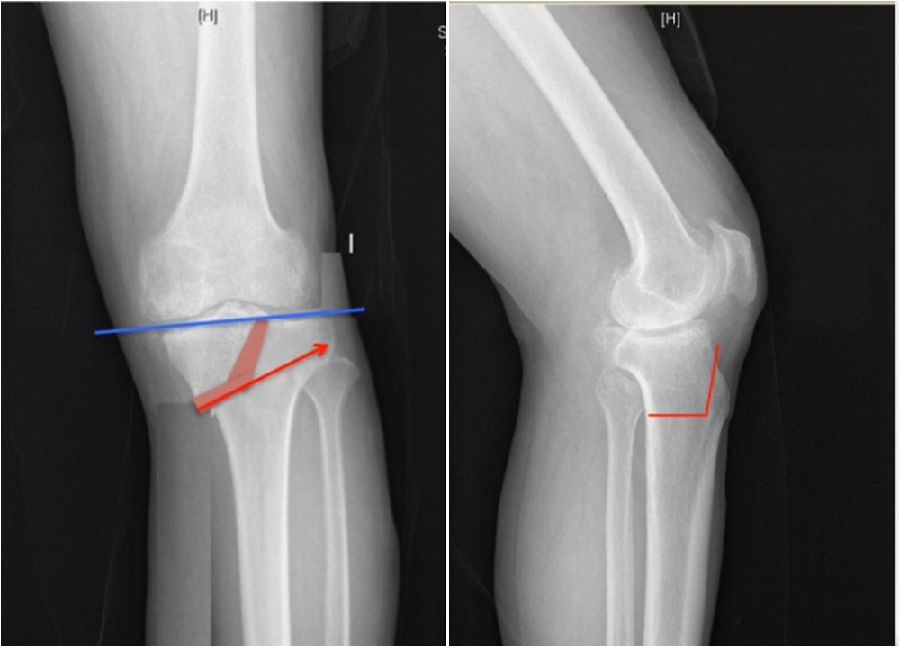

通过MAT测量全长片和内外侧应力位片,可以明确的测量出畸形的来源是股骨还是胫骨,有没有关节内磨损和韧带松弛。

膝MCOA病例,对线异常来源多个因素:胫骨畸形(MPTA异常),股骨形(mLDFA异常),胫骨平台塌陷,LCL松弛,内侧关节软骨丢失造成关节线不等宽等。MAT可以确定其中每种成分;应力下拍片,确定JLCA的关节松弛成分。关节软骨丢失占JLCA 3度,LCL松弛占JLCA 4度。

2、如何根据内侧间隙确定目标力线?

根据膝关节内侧间室模式程度选择个体化的目标力线。

关节间隙正常:目标MAD=0

关节间隙减少1/3:目标MAD =1/3Fujisawa点

关节间隙减少2/3:目标MAD =2/3Fujisawa点

关节间隙消失:目标MAD =3/3Fujisawa点